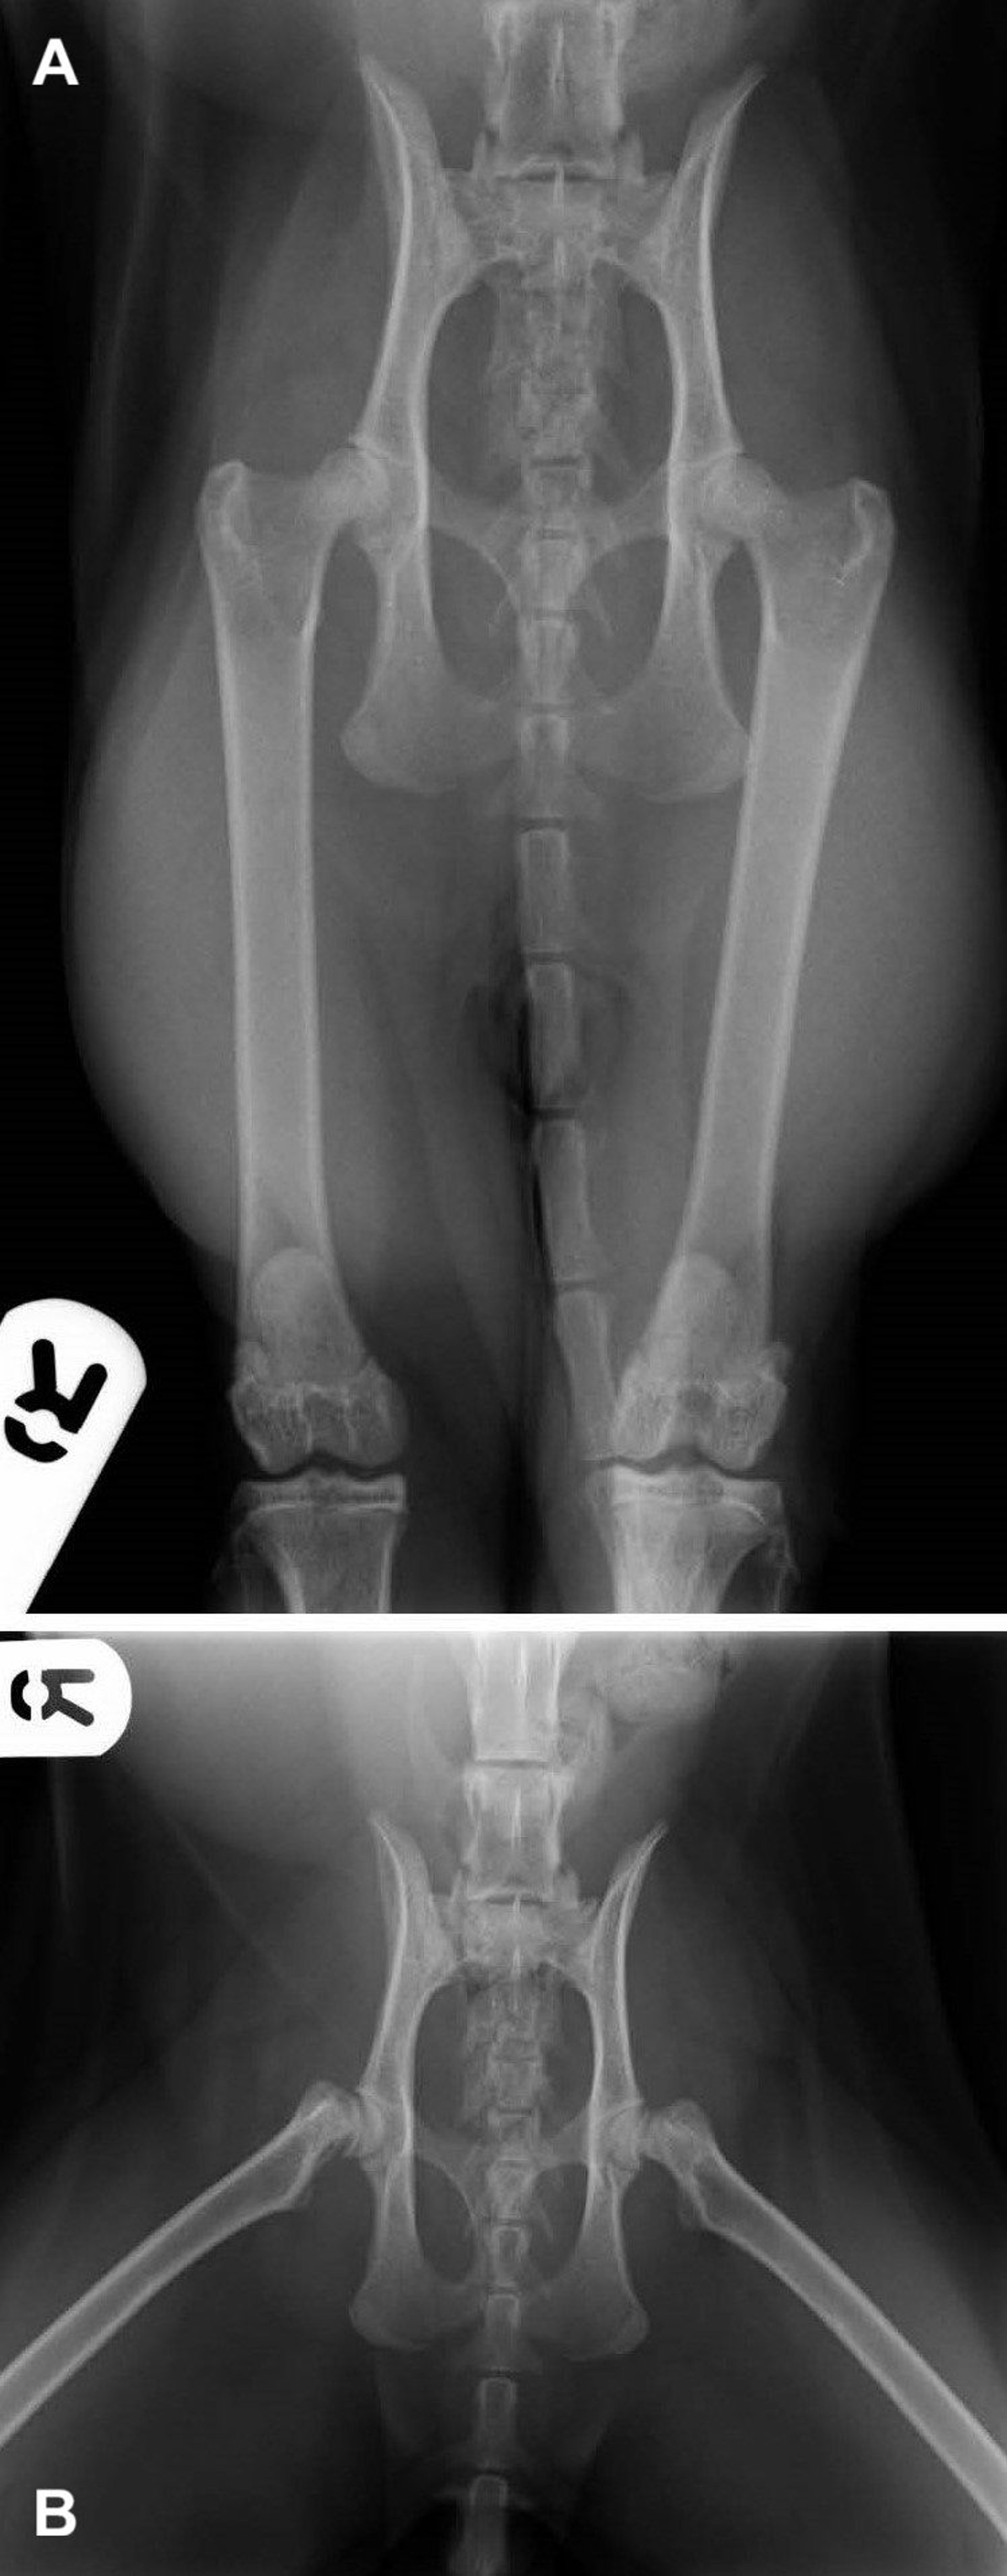

Capital physeal fracture, radiographs, cat

Ventrodorsal pelvic radiographs of a cat with a spontaneous slipped capital physeal fracture. (A) In this straight-limb view, the limb positioning (straight hindlimbs and reduction of the femoral head epiphysis) obscures the femoral epiphysis separation, so the fracture diagnosis cannot be confirmed. (B) This frog-leg (flexed) view reveals bilateral slipped capital physeal fracture of the femoral heads.

Courtesy of Dr. Pilar Lafuente.